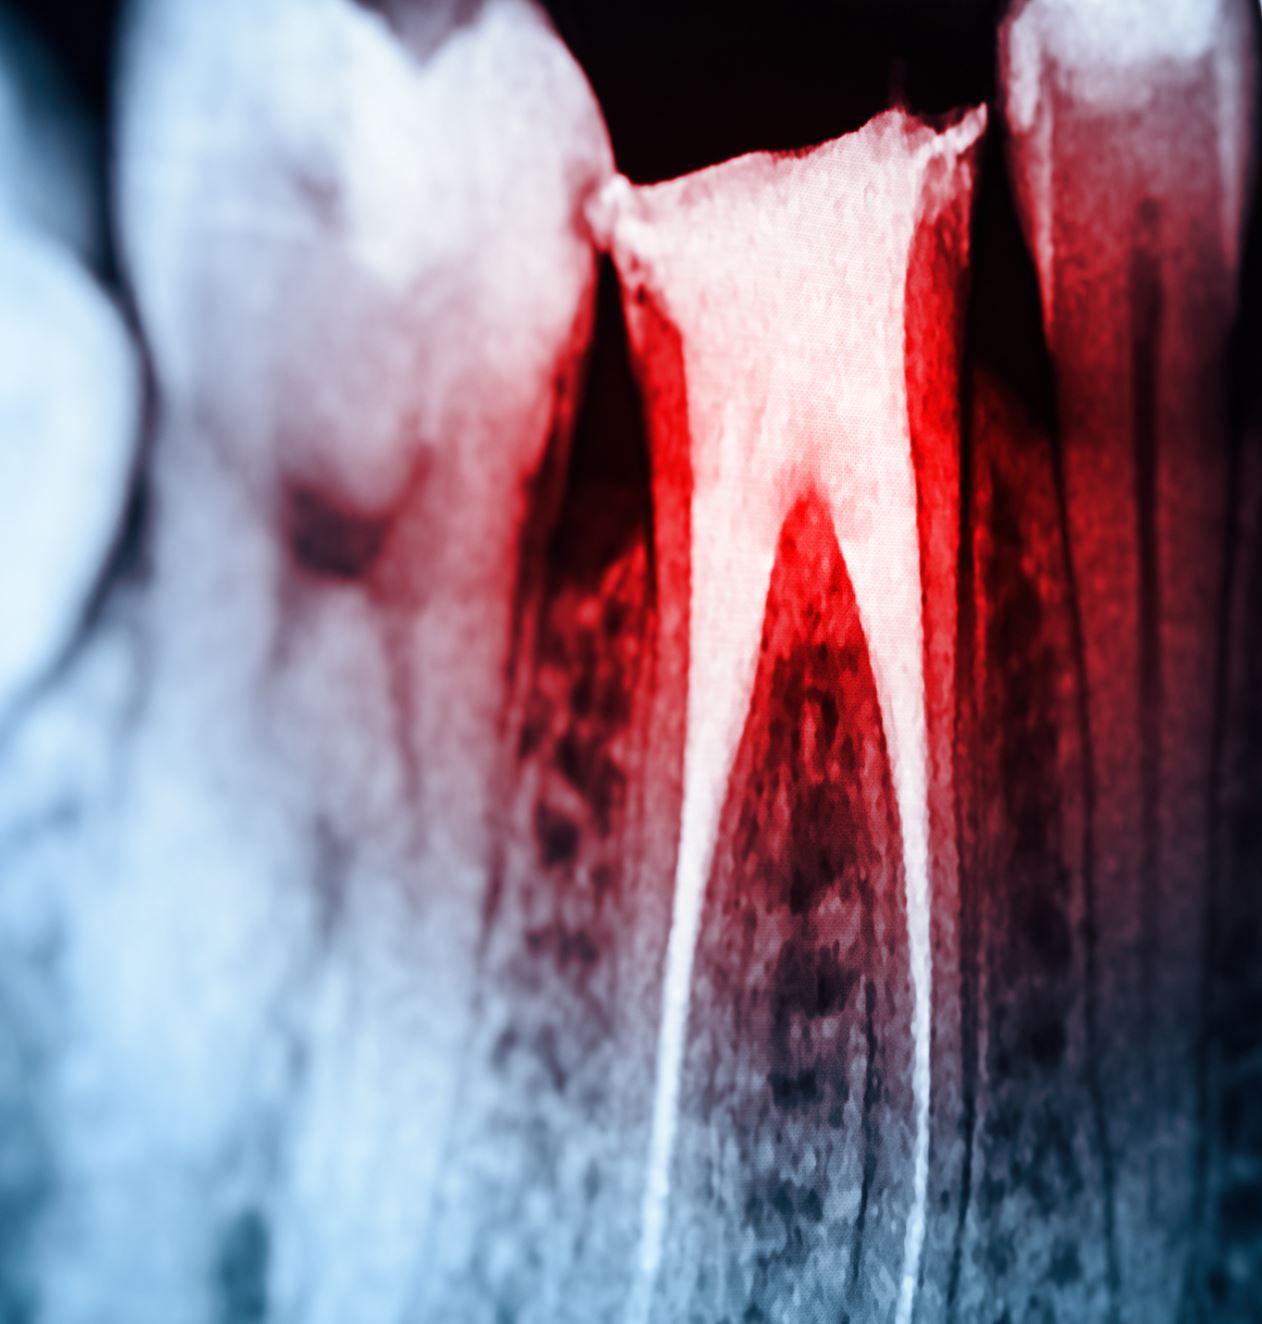

Die Präparation einer Zugangskavität stellt einen wichtigen Teilschritt der Wurzelkanalbehandlung dar. Ihre gute Vorbereitung und strukturierte Durchführung erleichtern nicht nur das Auffinden, sondern auch die Präparation, Desinfektion und Obturation aller Wurzelkanäle und tragen wesentlich zur Vermeidung vieler intraoperativer Probleme und Fehler bei.

Zahn 23: Pulpakavum ist vollständig dargestellt. Am Pulpakammerboden lassen sich alle vier Kanaleingänge identifizieren./© M. Hülsmann | Der Freie Zahnarzt (68)·12:58-68, Arztausweis/© Ulrich Zillmann / FotoMedienService / picture alliance (Symbolbild mit Fotomodell), Akten auf Tisch/© Julian Stratenschulte